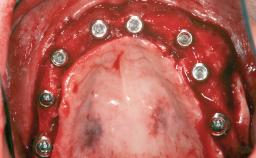

Le Fort I Interpositional Graft and Mandibular Sandwich Osteotomy for Maxillofacial Rehabilitation after Severe Periodontitis

# of Implants 14

Type of Implants Two-Piece

Bone Augmentation Horizontal|Sinus Floor Elevation|Staged|Vertical